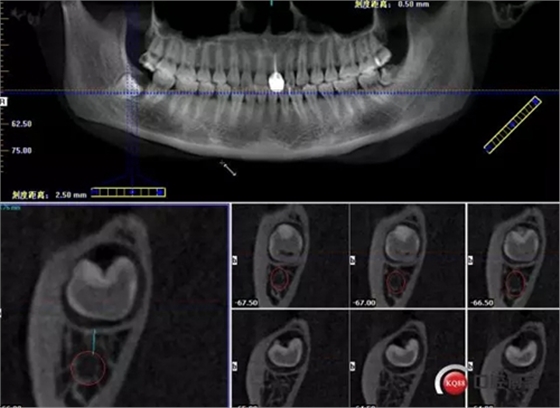

牙齒上1/3CT切片,神經(jīng)管在下方